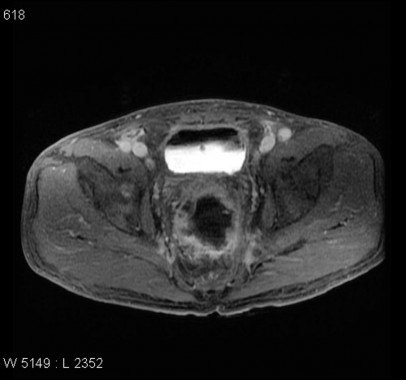

Cancer du rectum T4

Publié 12 mai 2015 à 1024 × 958 dans Tube digestif – Cancer du rectum [IRM]

Case courtesy of Dr Natalie Yang, Radiopaedia.org. From the case Rectal cancer – T4 – invading into prostate